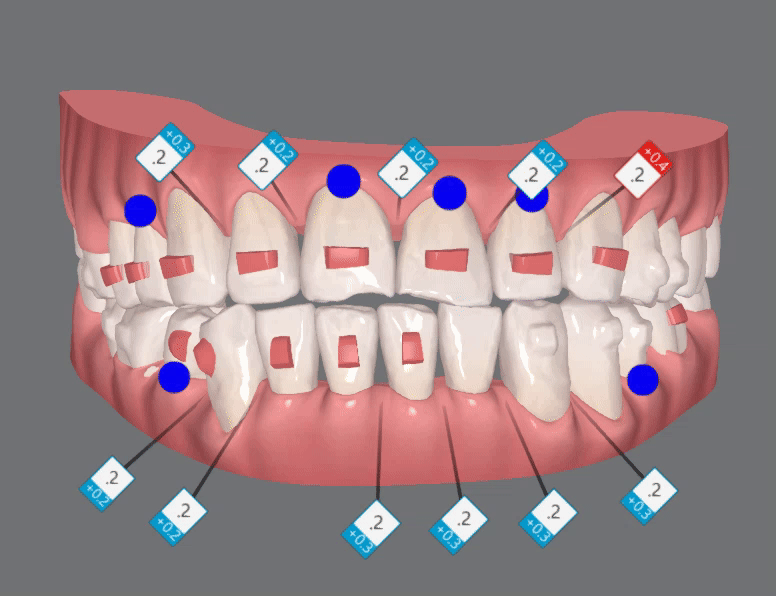

인비절라인은

치아에 부착되는 어태치먼트의 부착 여부, 위치, 어태치먼트의 종류 선택 등에 따라

치료결과가 확연히 달라질 수 있기때문에

2nd ClinCheck(19개)

두번째 클린체크는 19개의 장치를 통해

이전의 클린체크를 상호보완, 개선하여 마무리 해드렸습니다 :)

첫번째 클린체크에서 배열에 중점을 두었다면

두번째 클린체크에서는 교합을 개선시켜

윗니 아랫니들이

제 위치를 찾으며 정리가 되었습니다!!